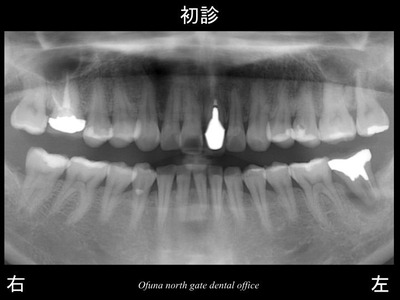

以下が初診時です。

下顎左側の一番奥歯が腫れているとのことで来院されました。

腫れた状態がかなり長くあったそうです。

しかし、腫れた時に薬を服用したりすると すぐ治るので

そのまま放置してしまったとのことです。

この悪い状態を放置したことが、大きな問題となるのです!

この歯は、歯根破折 していました。